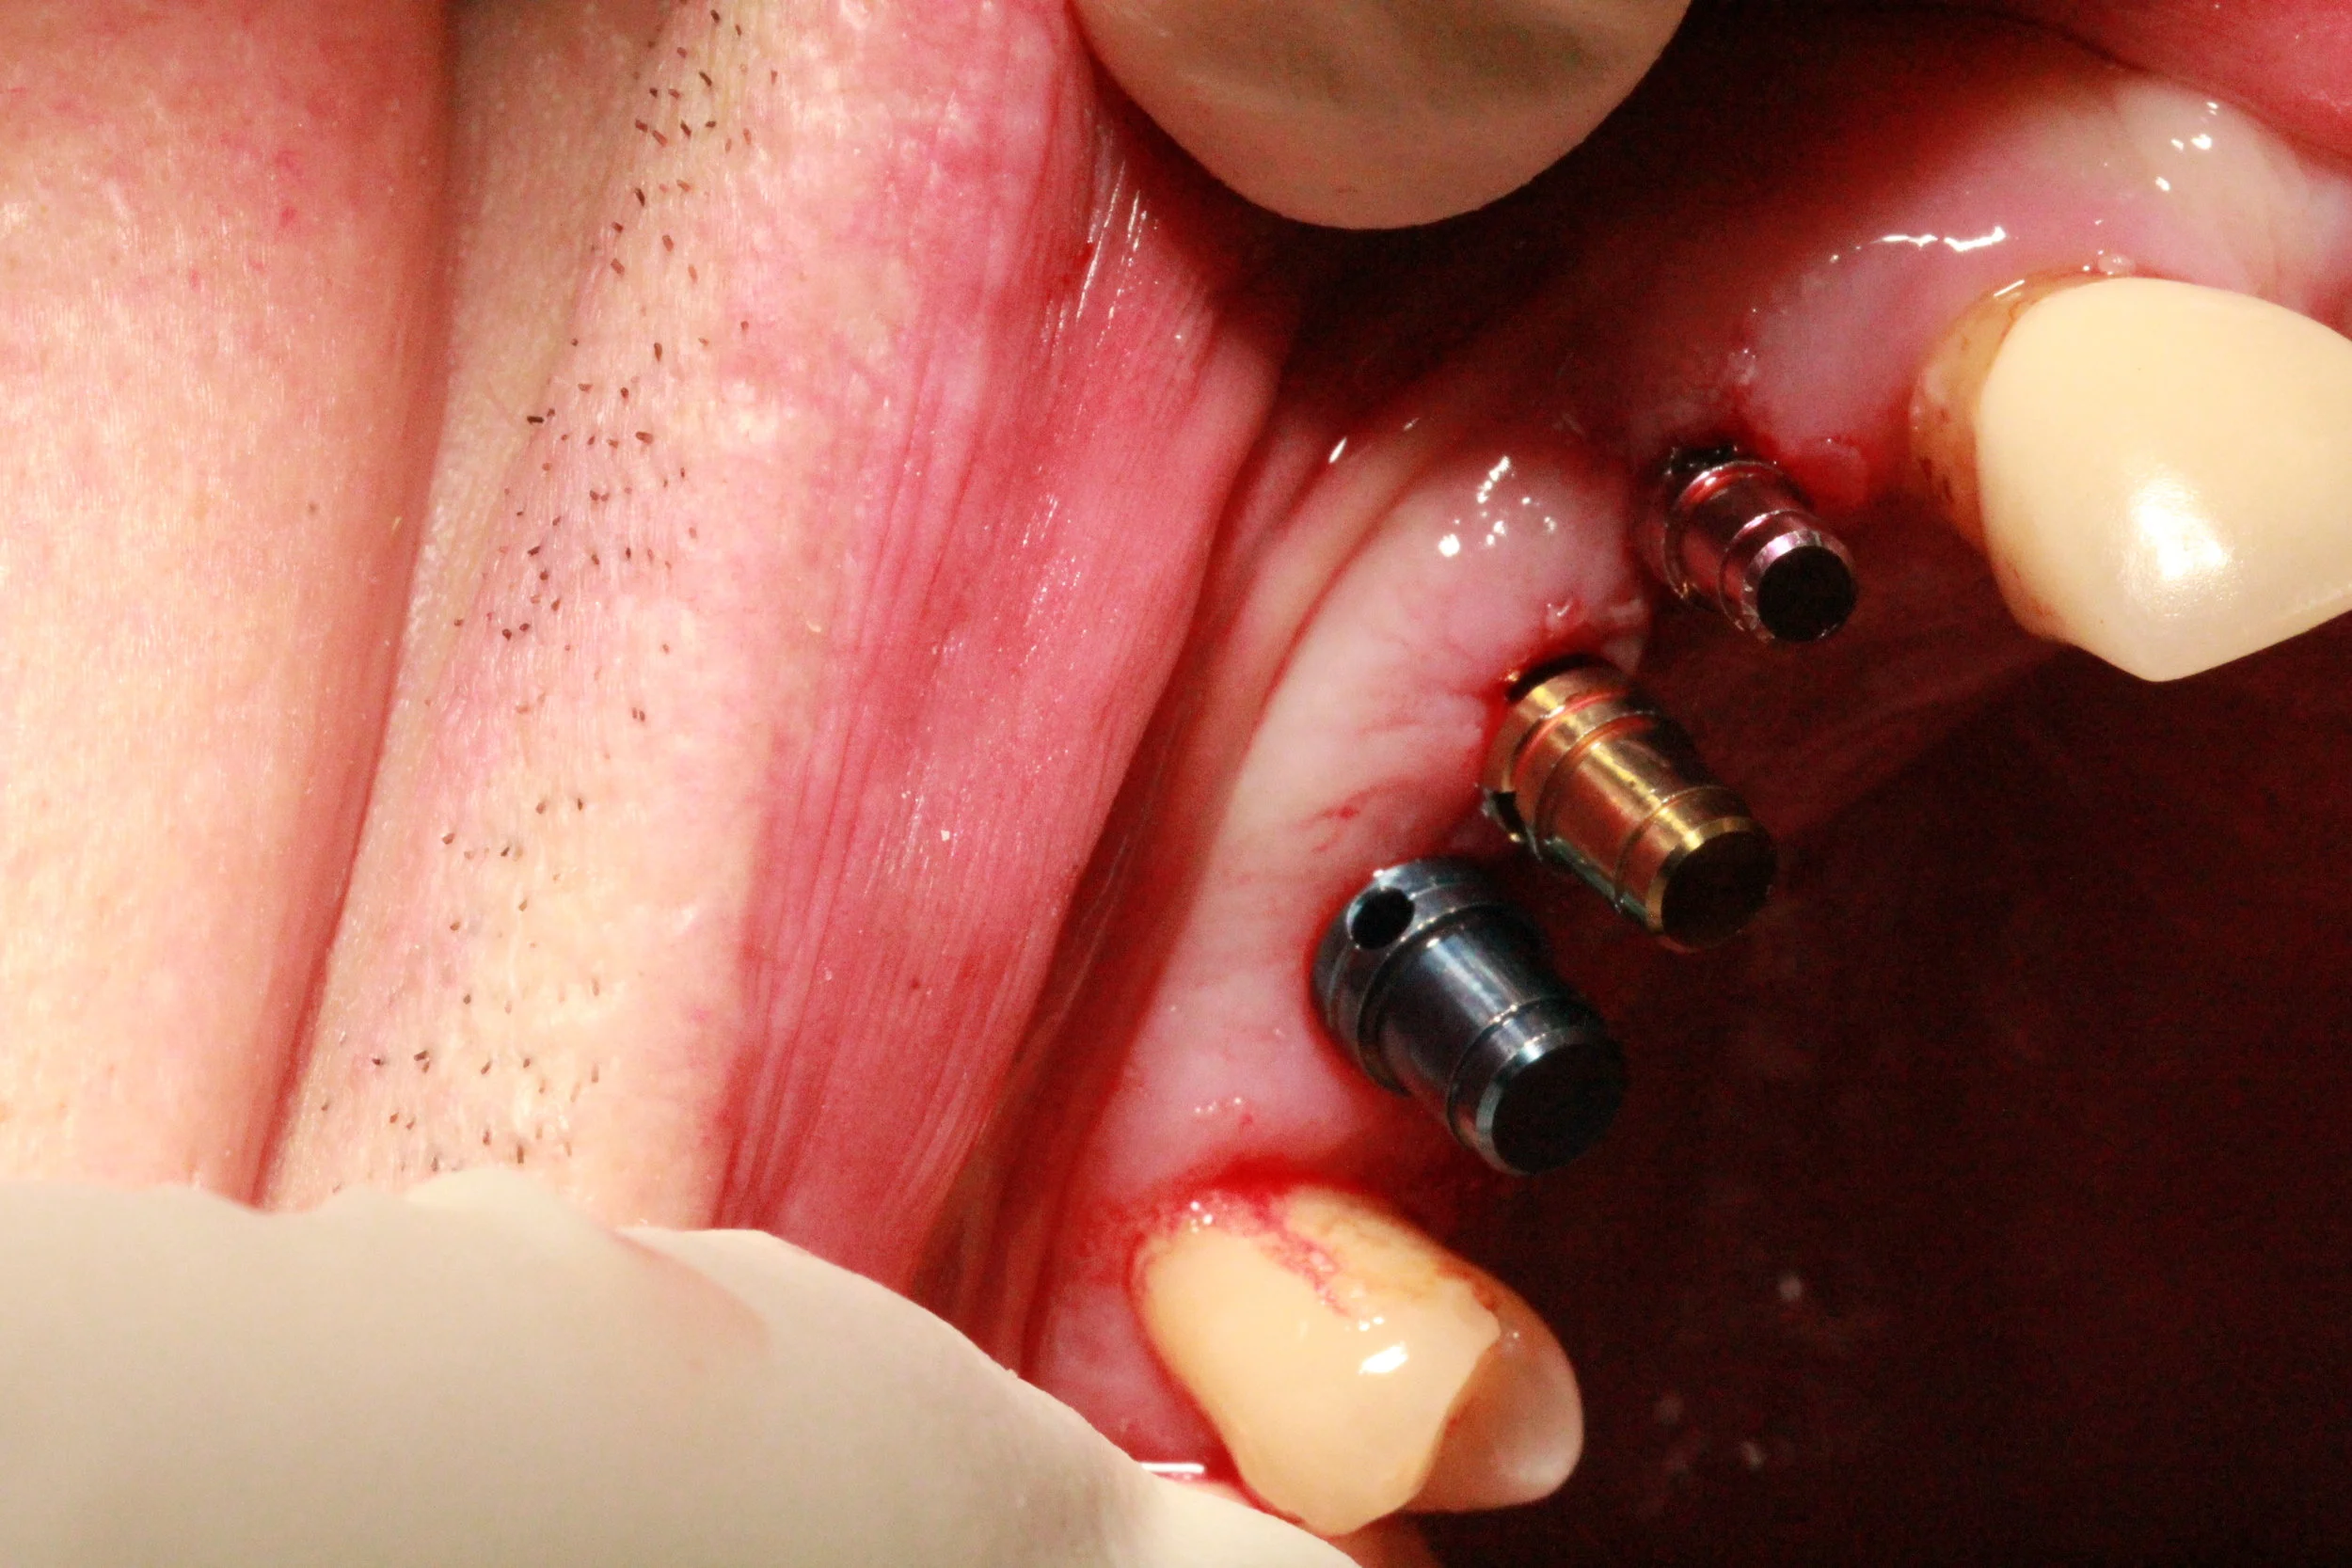

Implant Procedure Step 2 - Placing the implant - Part 2

Once the pilot hole has been made then the implantologist will use drill pieces of increasing sizes to slowly made the hole bigger. This allows the implantologist to slowly increase the length and width until they are happy with the size.

During the increasing sizes a thread will be made in the bone so that the implant will be able to be screwed in easily. Some implants can be self-tapping which means that they create there own space to fit.

Once the implantologist is happy they will often place a direction indicator in the pre-made hole this is just to assess what direction that the implant will be. They may also take x-rays with drill pieces in the hole as they are going along this is to make sure that everything is going as best it can and so that they can measure accurately.

Once they are happy with the size they will then screw in the implant. The implantologist here prefers to use a little wrench a do it by hand as he feels he gets the best results that way. However, some implantologists will use a machine that measures everthing for them.